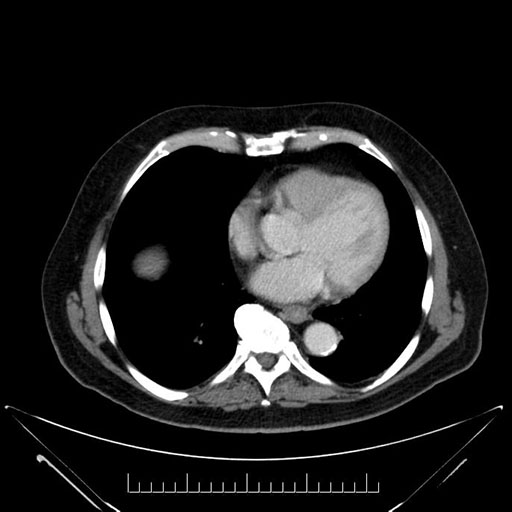

Imaging Analysis

Look through the patient's CT scan to identify any areas of concern for the necessary procedure.

Based on your CT findings, which issue(s) would give reason for "planned slowing down moment(s)" in this case?

Considering a standard Whipple procedure, what step(s) of the operation would you do differently in this case?